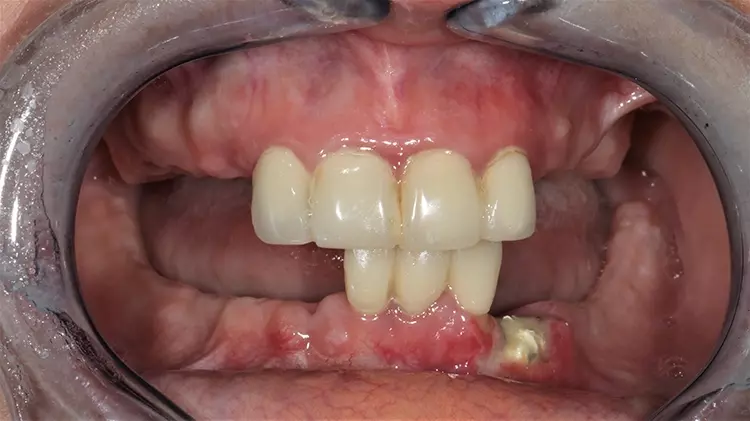

Abb. 2: Z. n. multiplen Zahnextraktionen alio loco / Zustand bei Erstvorstellung. SDS

Abb. 2: Z. n. multiplen Zahnextraktionen alio loco / Zustand bei Erstvorstellung.

Abb. 3: Z. n. multiplen Zahnextraktionen alio loco / Zustand bei Erstvorstellung. SDS

Abb. 3: Z. n. multiplen Zahnextraktionen alio loco / Zustand bei Erstvorstellung.

Im weiteren Behandlungsverlauf wurde die Patientin bei einem anderen Vorbehandler bereits festsitzend mit Titanimplantaten versorgt, welche jedoch aufgrund starker lokaler (Schmerzen, Entzündungen) sowie systemischer Reaktionen (u. a. Haarausfall, Hautausschläge) wieder entfernt wurden. Zum Zeitpunkt der Erstvorstellung der folgenden Behandlungsdokumentation war der Restzahnbestand nur noch auf die vier OK-Frontzähne und drei UK-Frontzähne mit voranschreitender Kieferatrophie beschränkt (Abb. 2 und 3).

Der Restzahnbestand war bereits mit provisorischen Kronen versorgt, welche allerdings bei der Erstvorstellung zu hoch eingestellt waren. Es wurde sich für die Sanierung mit Keramikimplantaten entschieden, um der Patientin eine langfristige, möglichst immunologisch neutrale Lösung bieten zu können [1].